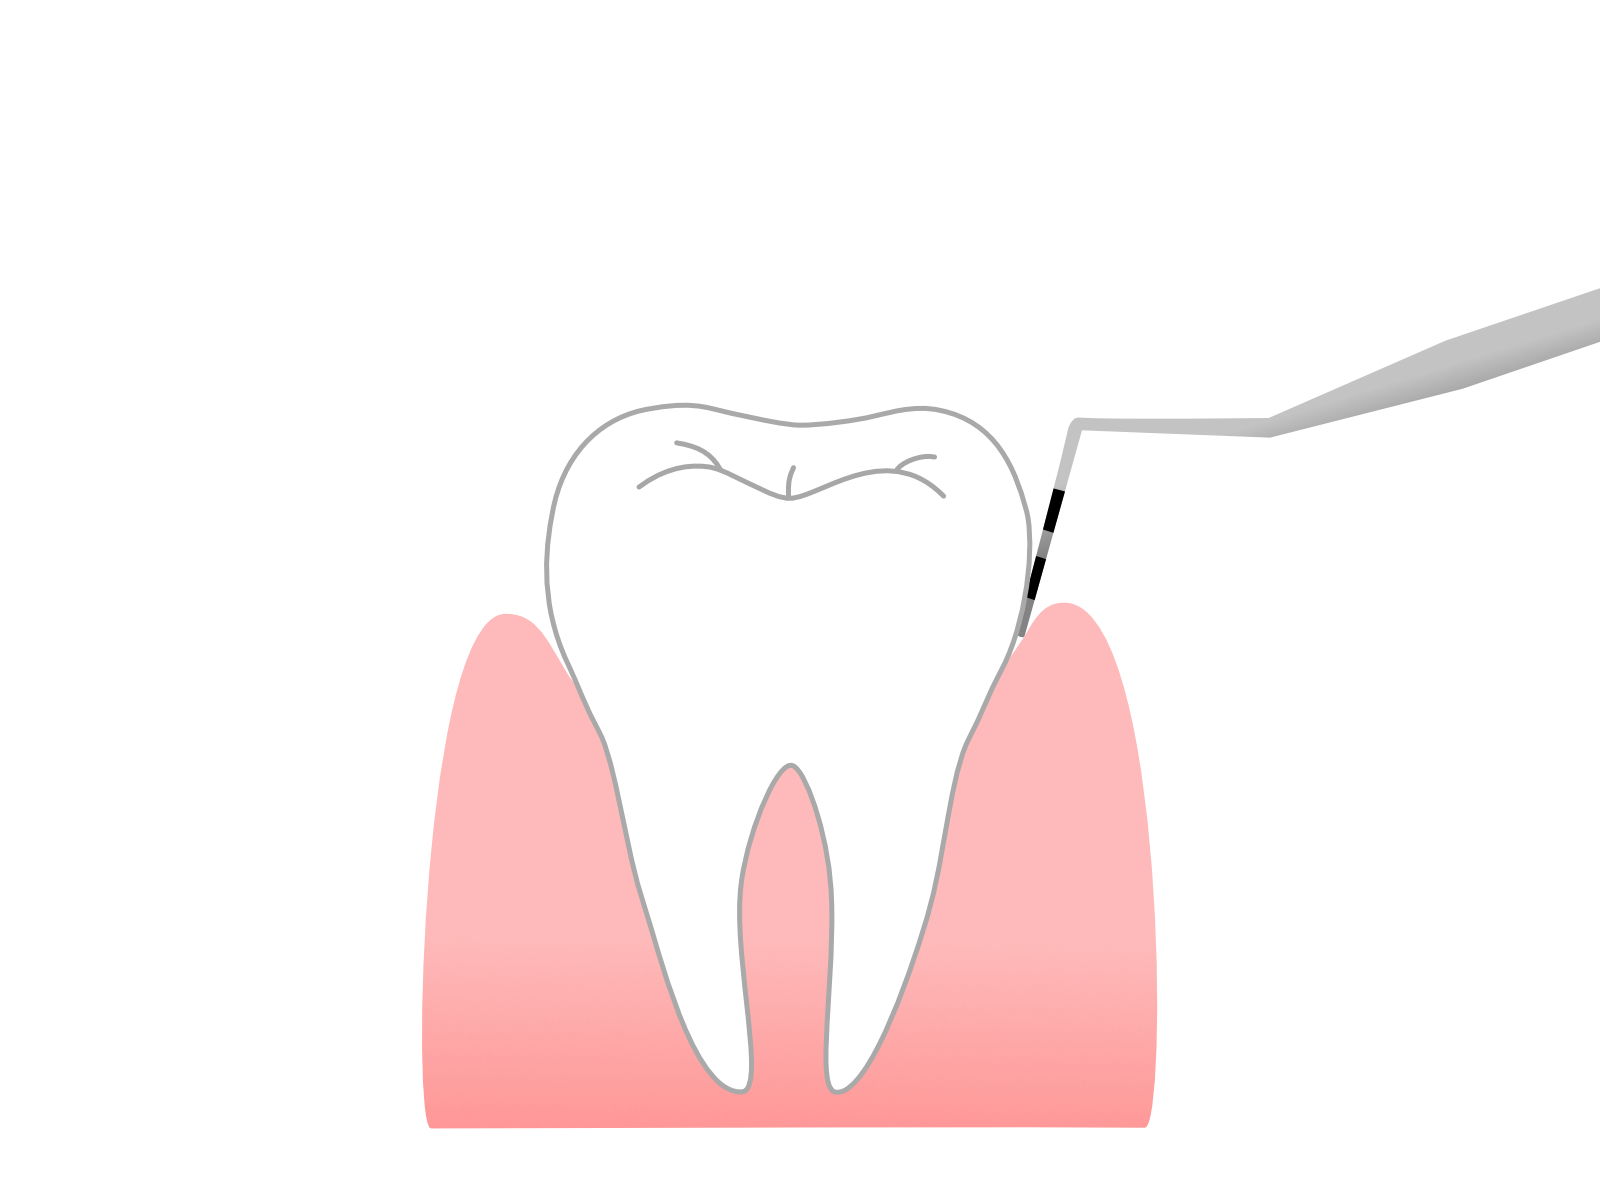

ポケット検査は、歯と歯茎の間の隙間(歯周ポケット)の深さを測る検査です。この隙間が深いと、歯周病が進んでいる可能性があります。歯周病の状態を正確に知るために重要な検査です。